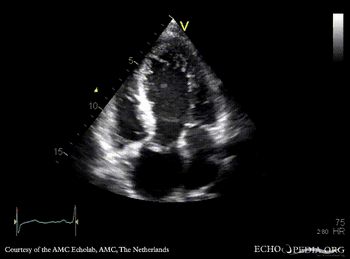

E00444.gif E00445.gif

PLAX: Color Doppler, severe aortic regurgitation A4CH: dilated left ventricle